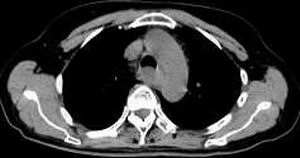

女,61岁,吞咽困难(包括开水)已久。

食道中上段癌并锁骨上窝淋巴结转移.

食道中上段中分化鳞癌伴锁骨上淋巴结转移